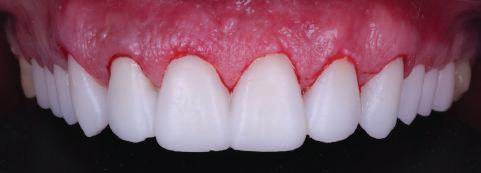

9Dental Tribune Bulgarian Edition / октомври 2022 г. След лечението За авторите: Д-р Манол Ивчев е създател на COLDY DENT Functional Atelier, завършва дентална медицина във ФДМ, София. Шест години е стажант в ортодонтска практика. Интересите му са изцяло насочени към функционалната дентална медицина. Посещава курсовете на Доусън и Льо Гал. Преминава редица обучения, акредитирани от Института на Славичек във Виена – VieSID. Впоследствие става най-младият инструктор във VieSID. Придобива права да преподава философията на проф. Рудолф Славичек в България. В практиката си се придържа към протоколите на Славичек за функционално лече ние и диагностика, тъй като те са насочени към комплексно лечение. Завършва всички нива за морфология на зъбите и моделаж при Janos Mako. Повишава знанията си по функционална ортодонтия чрез индивидуален курс в Румъния. Д-р Ивчев е и сертифициран зъболекар по лингвална ортодонтия от Катедрата по ортодонтия от Университета по стоматология в Тегу, Южна Корея. Сертифициран е и за лечение на ортодонтски аномалии чрез миофункционални апарати, а също и за ортодонтия, подпомагана от миниимпланти, отново от Университета по стоматология в Южна Корея. Завършва индивидуално обучение по функционална ортодонтия в Университета по дентална медицина в Богота, Колумбия, както и индивидуално обучение по функционална ортодонтия и физиотерапия по про токола на Mariano Rocabado. Има завършено индивидуално обучение по функционална зъботехника и функционален Wax-Up клас I,II и III. Завършва курс за Digital Smile Design и Skin Concept в Люксембург при Christian Coachman, Florin Cofar, Paulo Kano, Josef Kunkela, Livio Yoshinagа. Зт. Leandro Gambogi, Бразилия, завършва зъботехника през 1999 г. Експерт и пионер в дигиталната диагностика. Лектор и инструктор на курсове в областта на дигиталното протезиране. Понастоящем е главен изпълнителен директор и зъботехник в DENTALE DIGITAL LAB. В периода януари 2005 г. – декември 2006 г. завършва бизнес управление и администрация в Methodist University Center Izabela Hendrix. Съавтор на книгата Odontologia Digital: Desafiando os Limites, глава 5: „Дигитално включване във времето. Технология CAD/CAM“. Преминал множество обучения при световноизвестни кли ницисти. Фиг. 51 Фиг. 54 Фиг. 57 Фиг. 58 Фиг. 63 Фиг. 64 Фиг. 65 Фиг. 59 Фиг. 61 Фиг. 62 Фиг. 60 Фиг. 55 Фиг. 56 Фиг. 52 Фиг. 53 Фиг. 66

Една седмица след препарацията на зъбите и циментирането на цирко ниевото кепе бяха изработени 12 IPS Empress Cad Multi фасети. Макро- и микротекстурата на фасе тите бяха направени на ръка, след кое то бяха нанесени 3D характеризации с боички, а полирането отново бе напра вено ръчно, за да им се придаде естест вен и естетичен вид. Предизвикателството тук беше короната да има същите оптични характеристики като тези на остана лите зъби при естествена светлина, през поляризационен и флуоресцентен филтър. 3D принтерът бе Fromlabs, софтуерът за фрезоване – Mill Box, а фрез апаратът –imes icore CORiTEC 350i. В крайна сметка постигнахме ес тествен вид на усмивката с натурал на зъбна морфология при изцяло диги тален протокол, при който дизайнът бе направен първоначално и през всич ки етапи на лечението се придържахме към него до самия край Излишно е да отбелязваме, че всички сме удовлетворени от постигнатото! Преди След Победител в категория „Клиничен случай с изцяло дигитален протокол“ в конкурса „Усмивка на годината 2022“